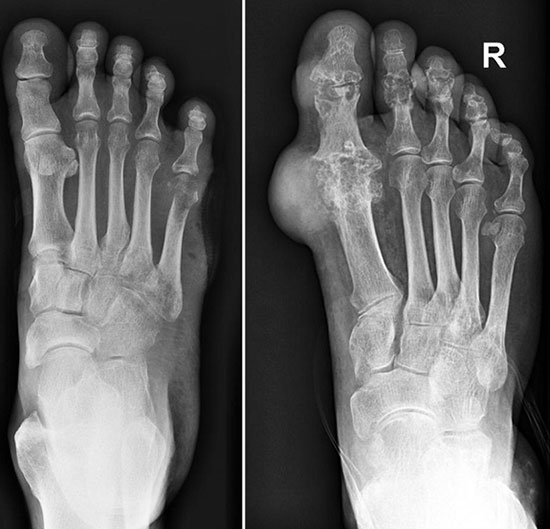

• рентгенографию – поможет обнаружить патологические процессы в суставе;

Рентген здоровой ступни (слева на фото) и пораженной подагрой (справа)

рентген здоровой ступни и пораженной подагрой